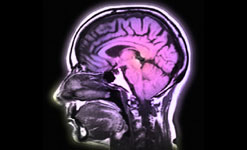

Our reporter Molly Bentley checks in from San Francisco with the news that scientists at the University of Southern California have been studying the brains of pathological liars and found that they have more white matter - and less grey matter - in their brains than those of us who just tell the odd porkie. This helps us understand people with Autism, who are unable to lie.